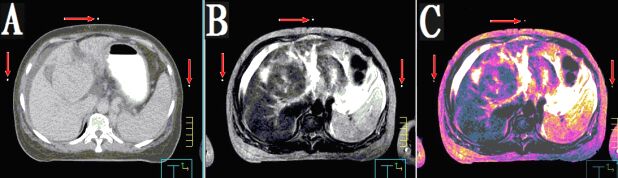

本產(chǎn)品主要適用于不同模態(tài)圖像引導(dǎo)下放療時(shí)定位,定點(diǎn)經(jīng)皮穿刺活檢或積液抽吸引流,不同模態(tài)間圖像融合控制點(diǎn)配準(zhǔn)等。

3.??同一定位貼,在多種模態(tài)掃描下成像均能顯示為點(diǎn)狀,可用作圖像融合的共同配準(zhǔn)控制點(diǎn),大小、位置一致,方便全身或軀段臟器異機(jī)圖像融合,精度高,易開展新的臨床應(yīng)用。

CT和MR通用型:具有同一個(gè)定位球在CT掃描高密度、MR常規(guī)掃描高信號(hào)的特點(diǎn),主要用于

CT/MR圖像融合,更換掃描設(shè)備,不需要更換標(biāo)記點(diǎn)。型號(hào)MK⊙CT/MR,每盒三貼;